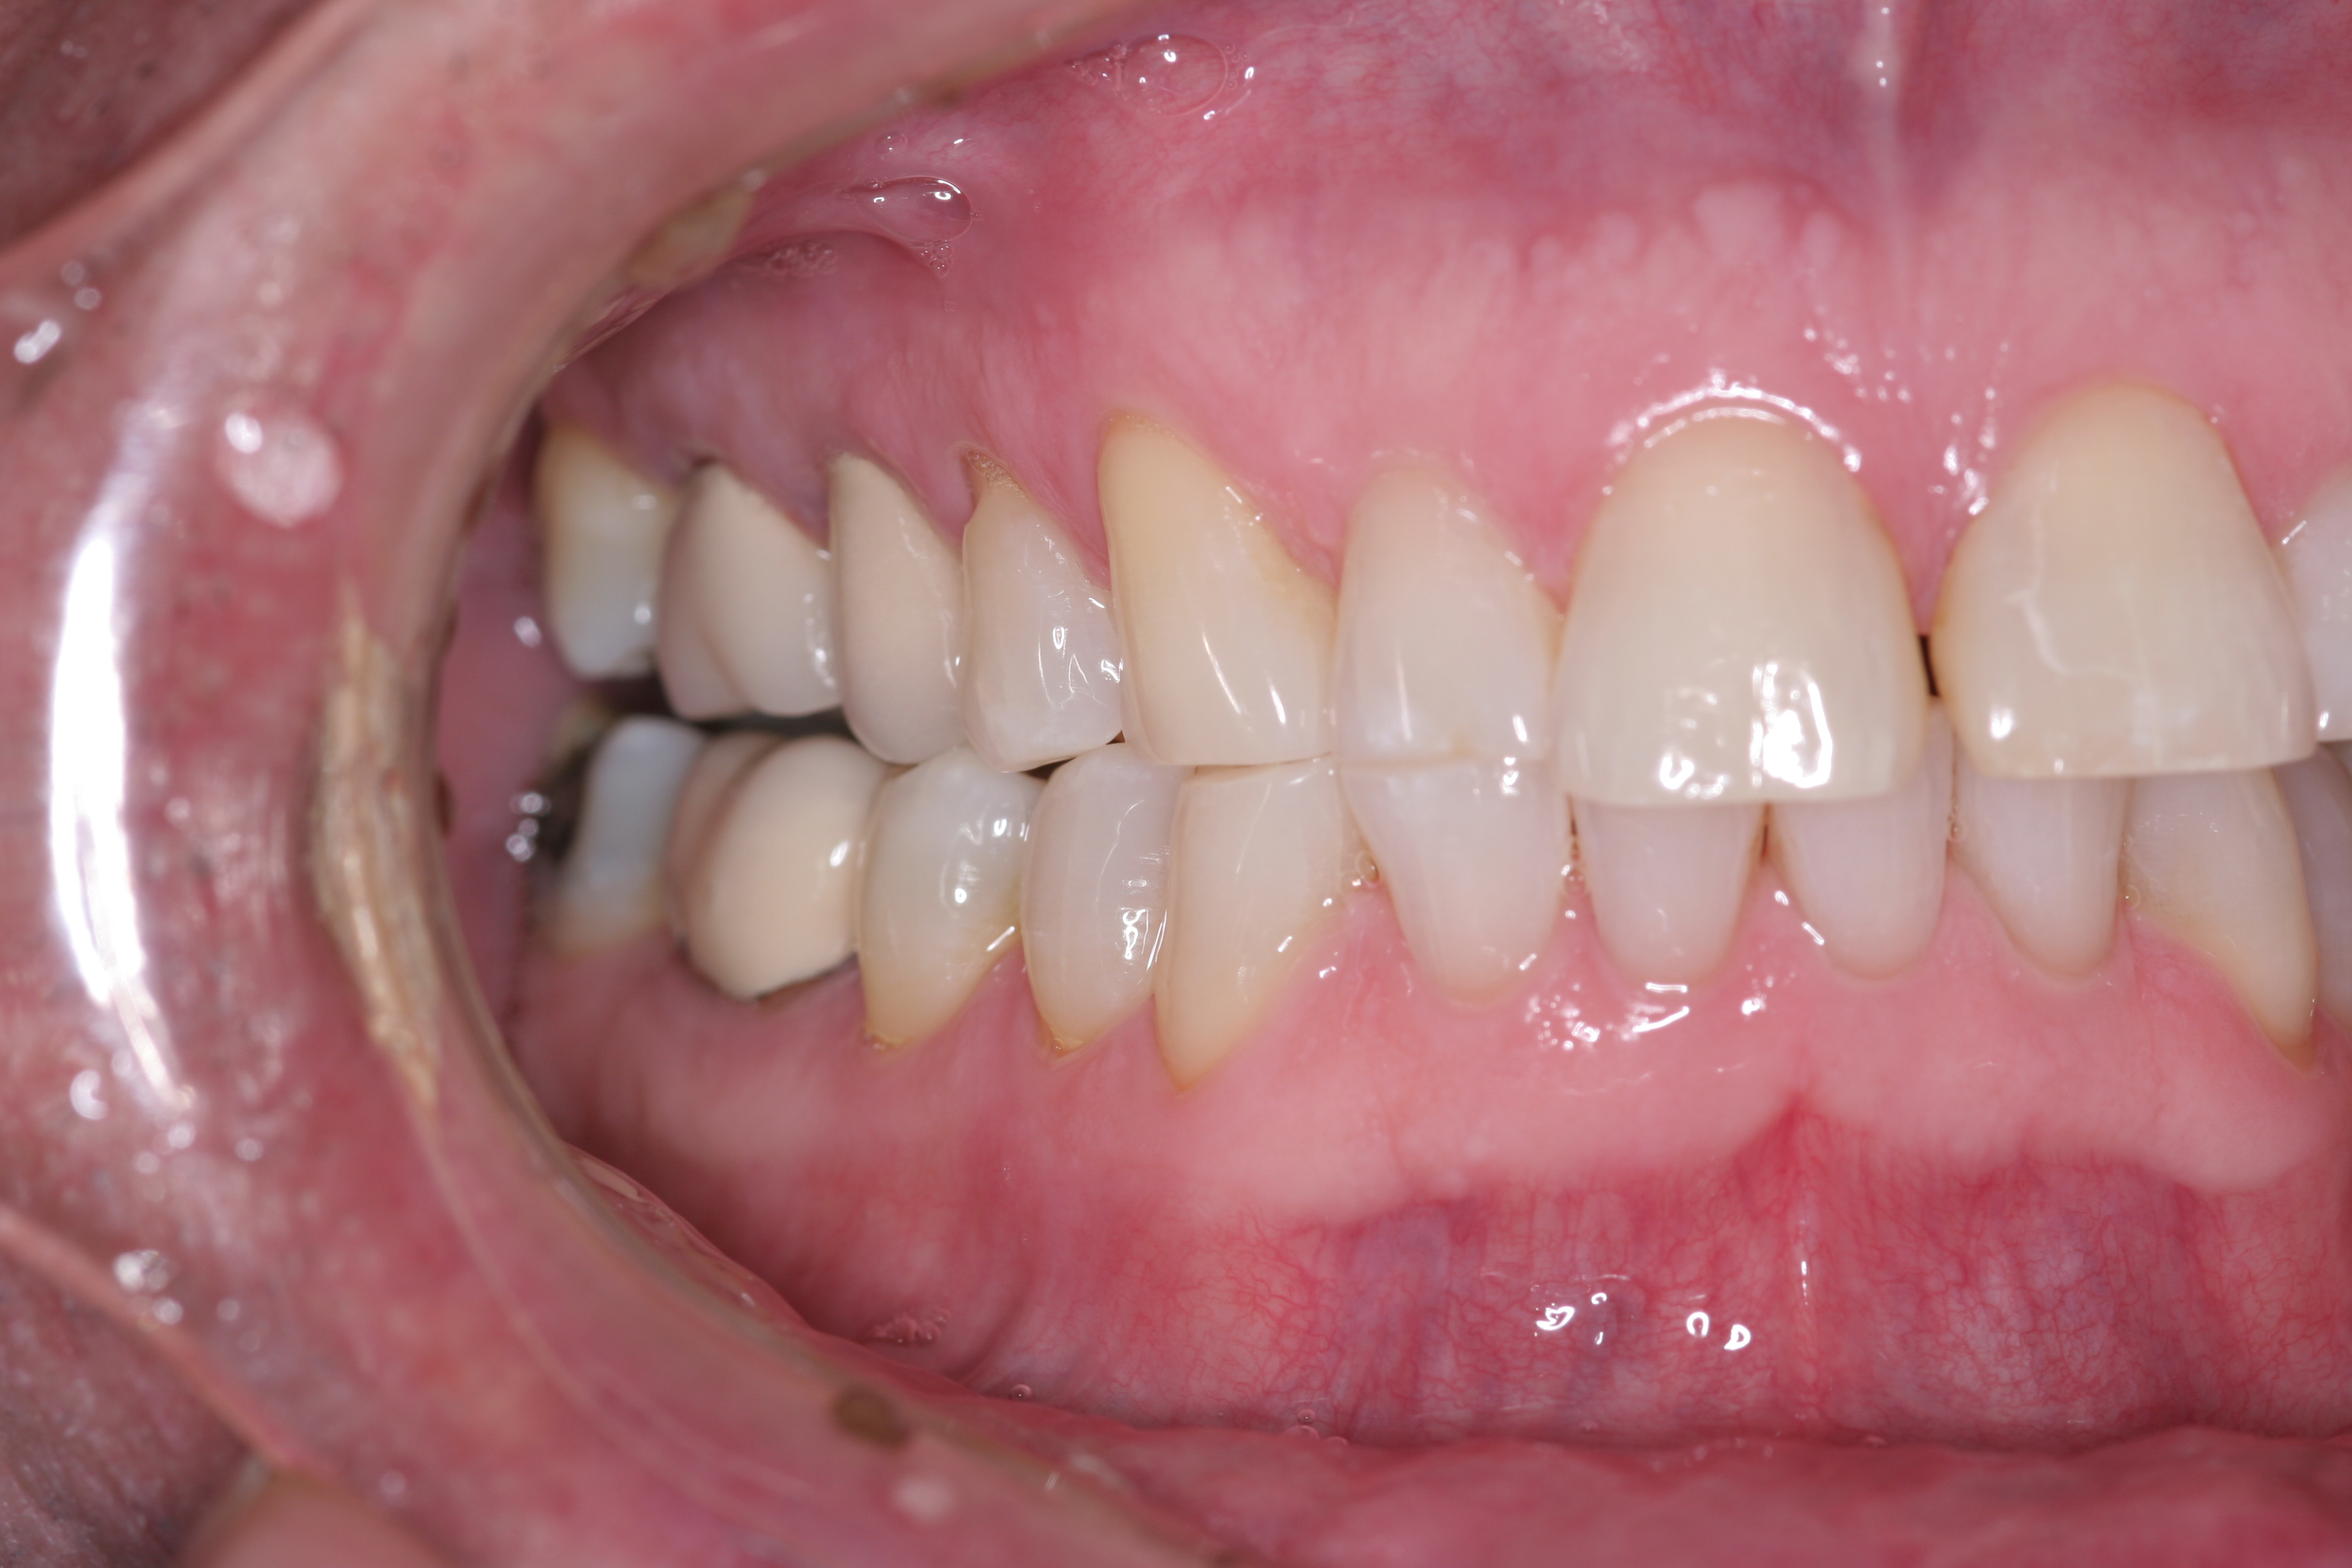

Treatment for this patient included posterior reductive equilibration and additive anterior equilibration (restoration) to eliminate the CR/MIP interferences and to meet the requirements of occlusal stability. Teeth Nos. 5 through 11 and 22 through 27 were prepared for full-coverage lithium-disilicate restorations. Crestal bone heights were evaluated. Soft-tissue crown lengthening was performed on the maxillary anterior teeth by a soft-tissue diode as needed. The esthetic, functional, and phonetic changes were evaluated and confirmed in the provisional restorative phase (Figure 17 through Figure 21).

Once approved, impressions of the provisionals were taken so the laboratory could precisely copy the 3D position of the anterior teeth as successfully proven in the provisionals. The postoperative result and final functional photographs are shown in Figure 22 through Figure 29. Posterior treatment can now be completed in segments as necessary. Posterior morphology will be developed in harmony with the now corrected anterior contour and functional parameters. The fulfillment of the previously mentioned requirements of occlusal stability were evaluated and refined in the final restorations. The patient was placed in a posttreatment dual-arch B splint appliance to help manage any further parafunctional forces should they occur.

(22.) The final restorations, which reflect the changes modeled through the provisional phase.

Figure 22

(23.) The final restorations, which reflect the changes modeled through the provisional phase.

Figure 23

(24.) The final restorations, which reflect the changes modeled through the provisional phase.

Figure 24

(25.) The final restorations, which reflect the changes modeled through the provisional phase.

Figure 25

(26.) The final restorations, which reflect the changes modeled through the provisional phase.

Figure 26

(27.) The final restorations, which reflect the changes modeled through the provisional phase.

Figure 27

(28.) The final restorations, which reflect the changes modeled through the provisional phase.

Figure 28

(29.) The final restorations, which reflect the changes modeled through the provisional phase.

Figure 29